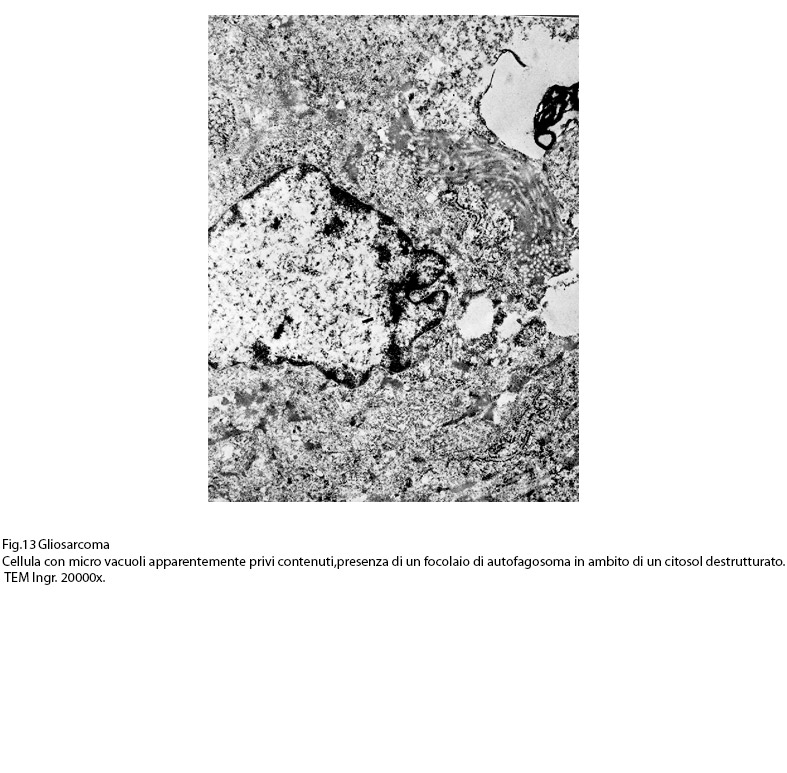

Fig.13  Fig.14